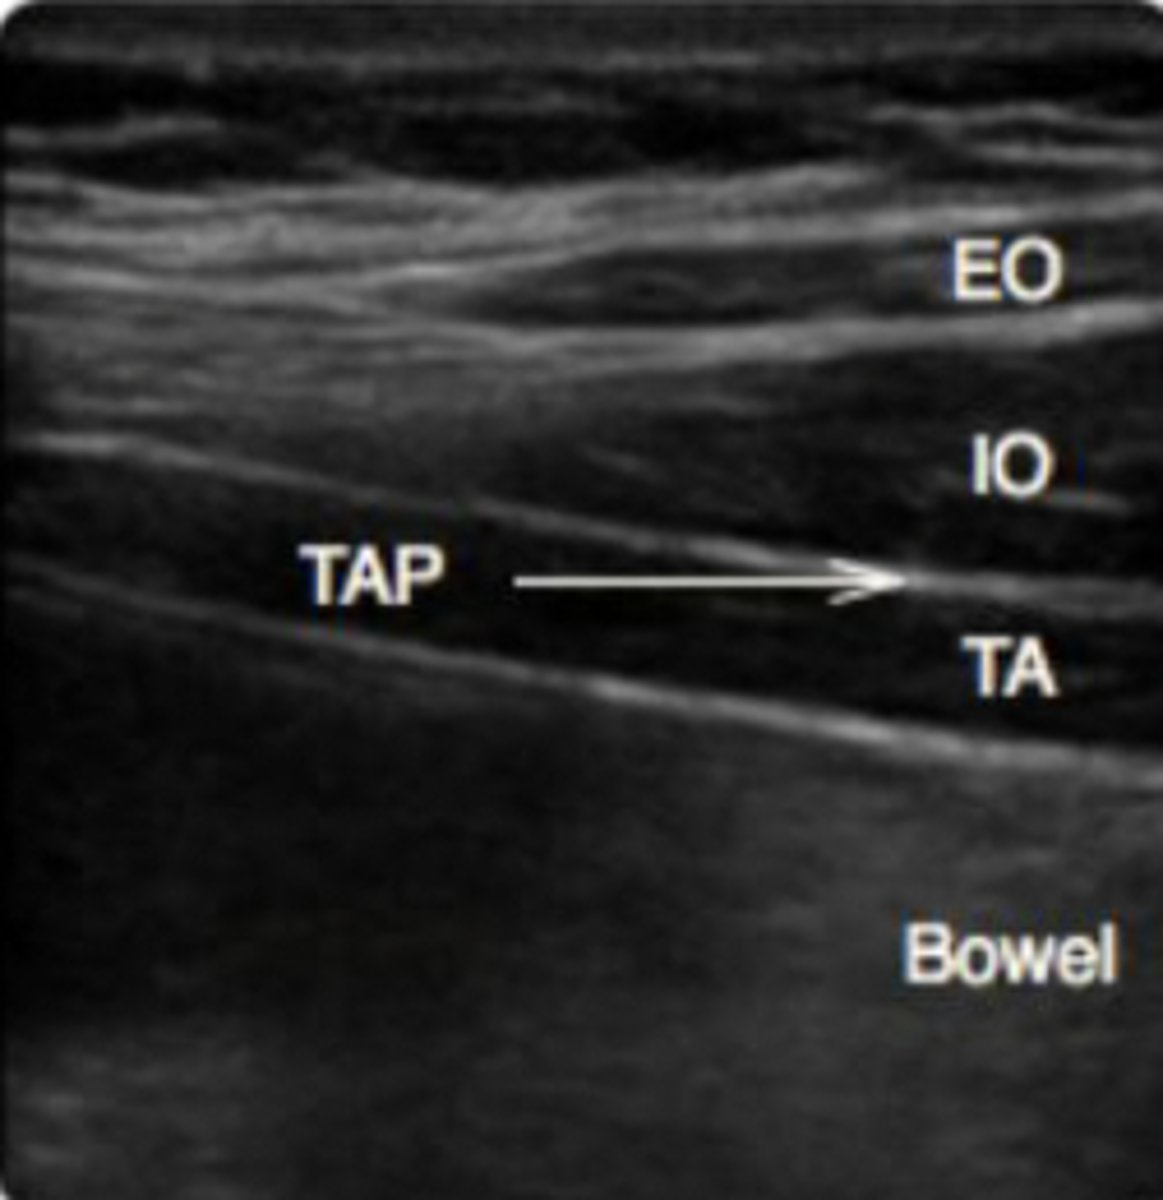

What pt populations benefit from a TAP block?

-unilateral PNB targets n of anterior and lateral abd wall

-abd procedures (gen, GYN, uro) that involve T9-L1 distribution

-Bilateral blocks req for a midline incision or laparoscopic Sx

Describe the anatomy required to perform a TAP block

Superficial to deep:

-Subq tissue

-External oblique m

-internal oblique m

-transverse abdominis m

-peritoneum

Describe the landmarks required to perform a TAP block

Form triangle of Petit:

-Latissimus dorsi m

-iliac crest